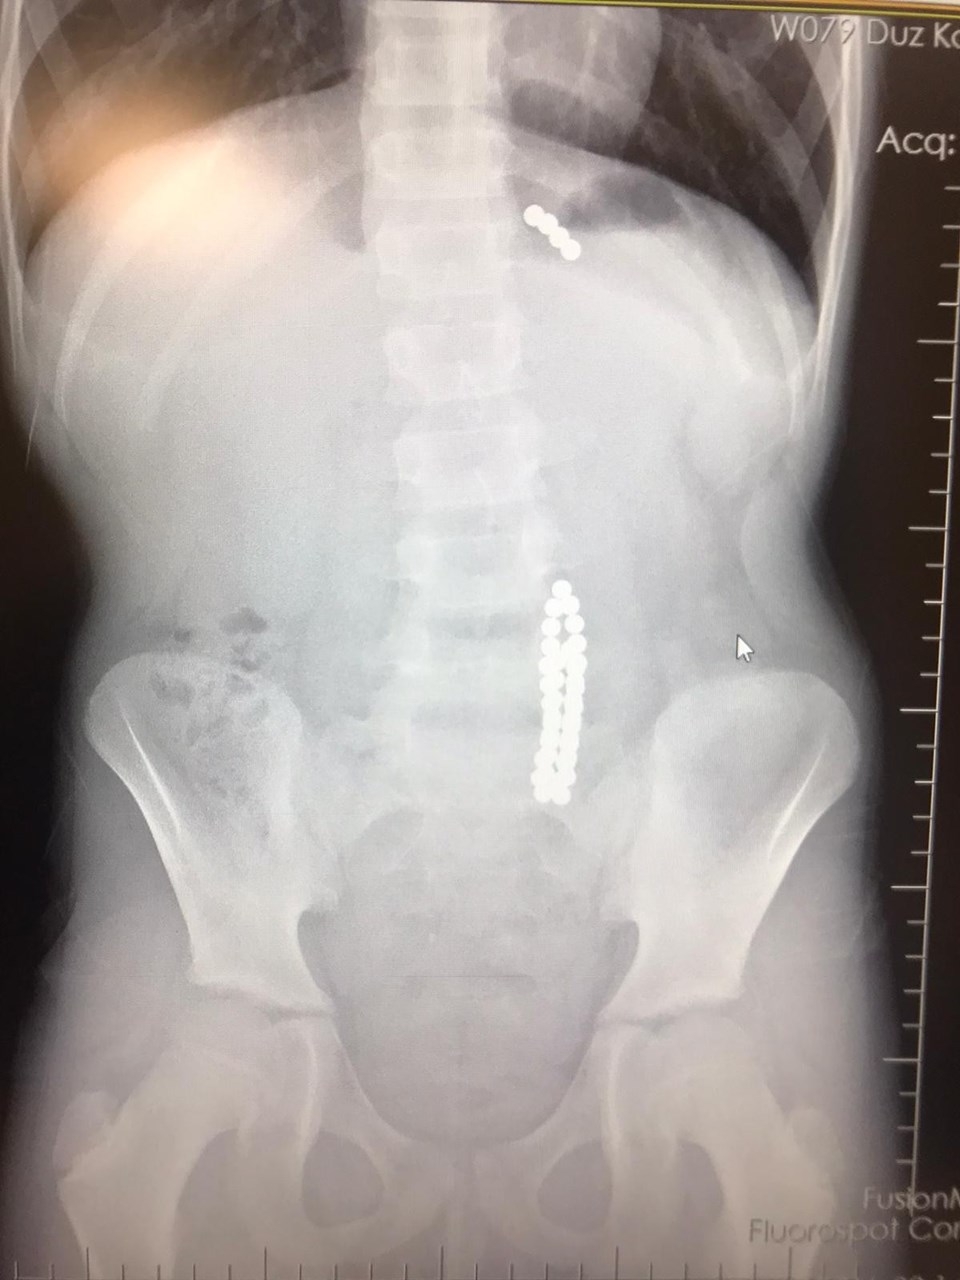

Çocuğun midesinden 42 adet mıknatıs topu çıktı